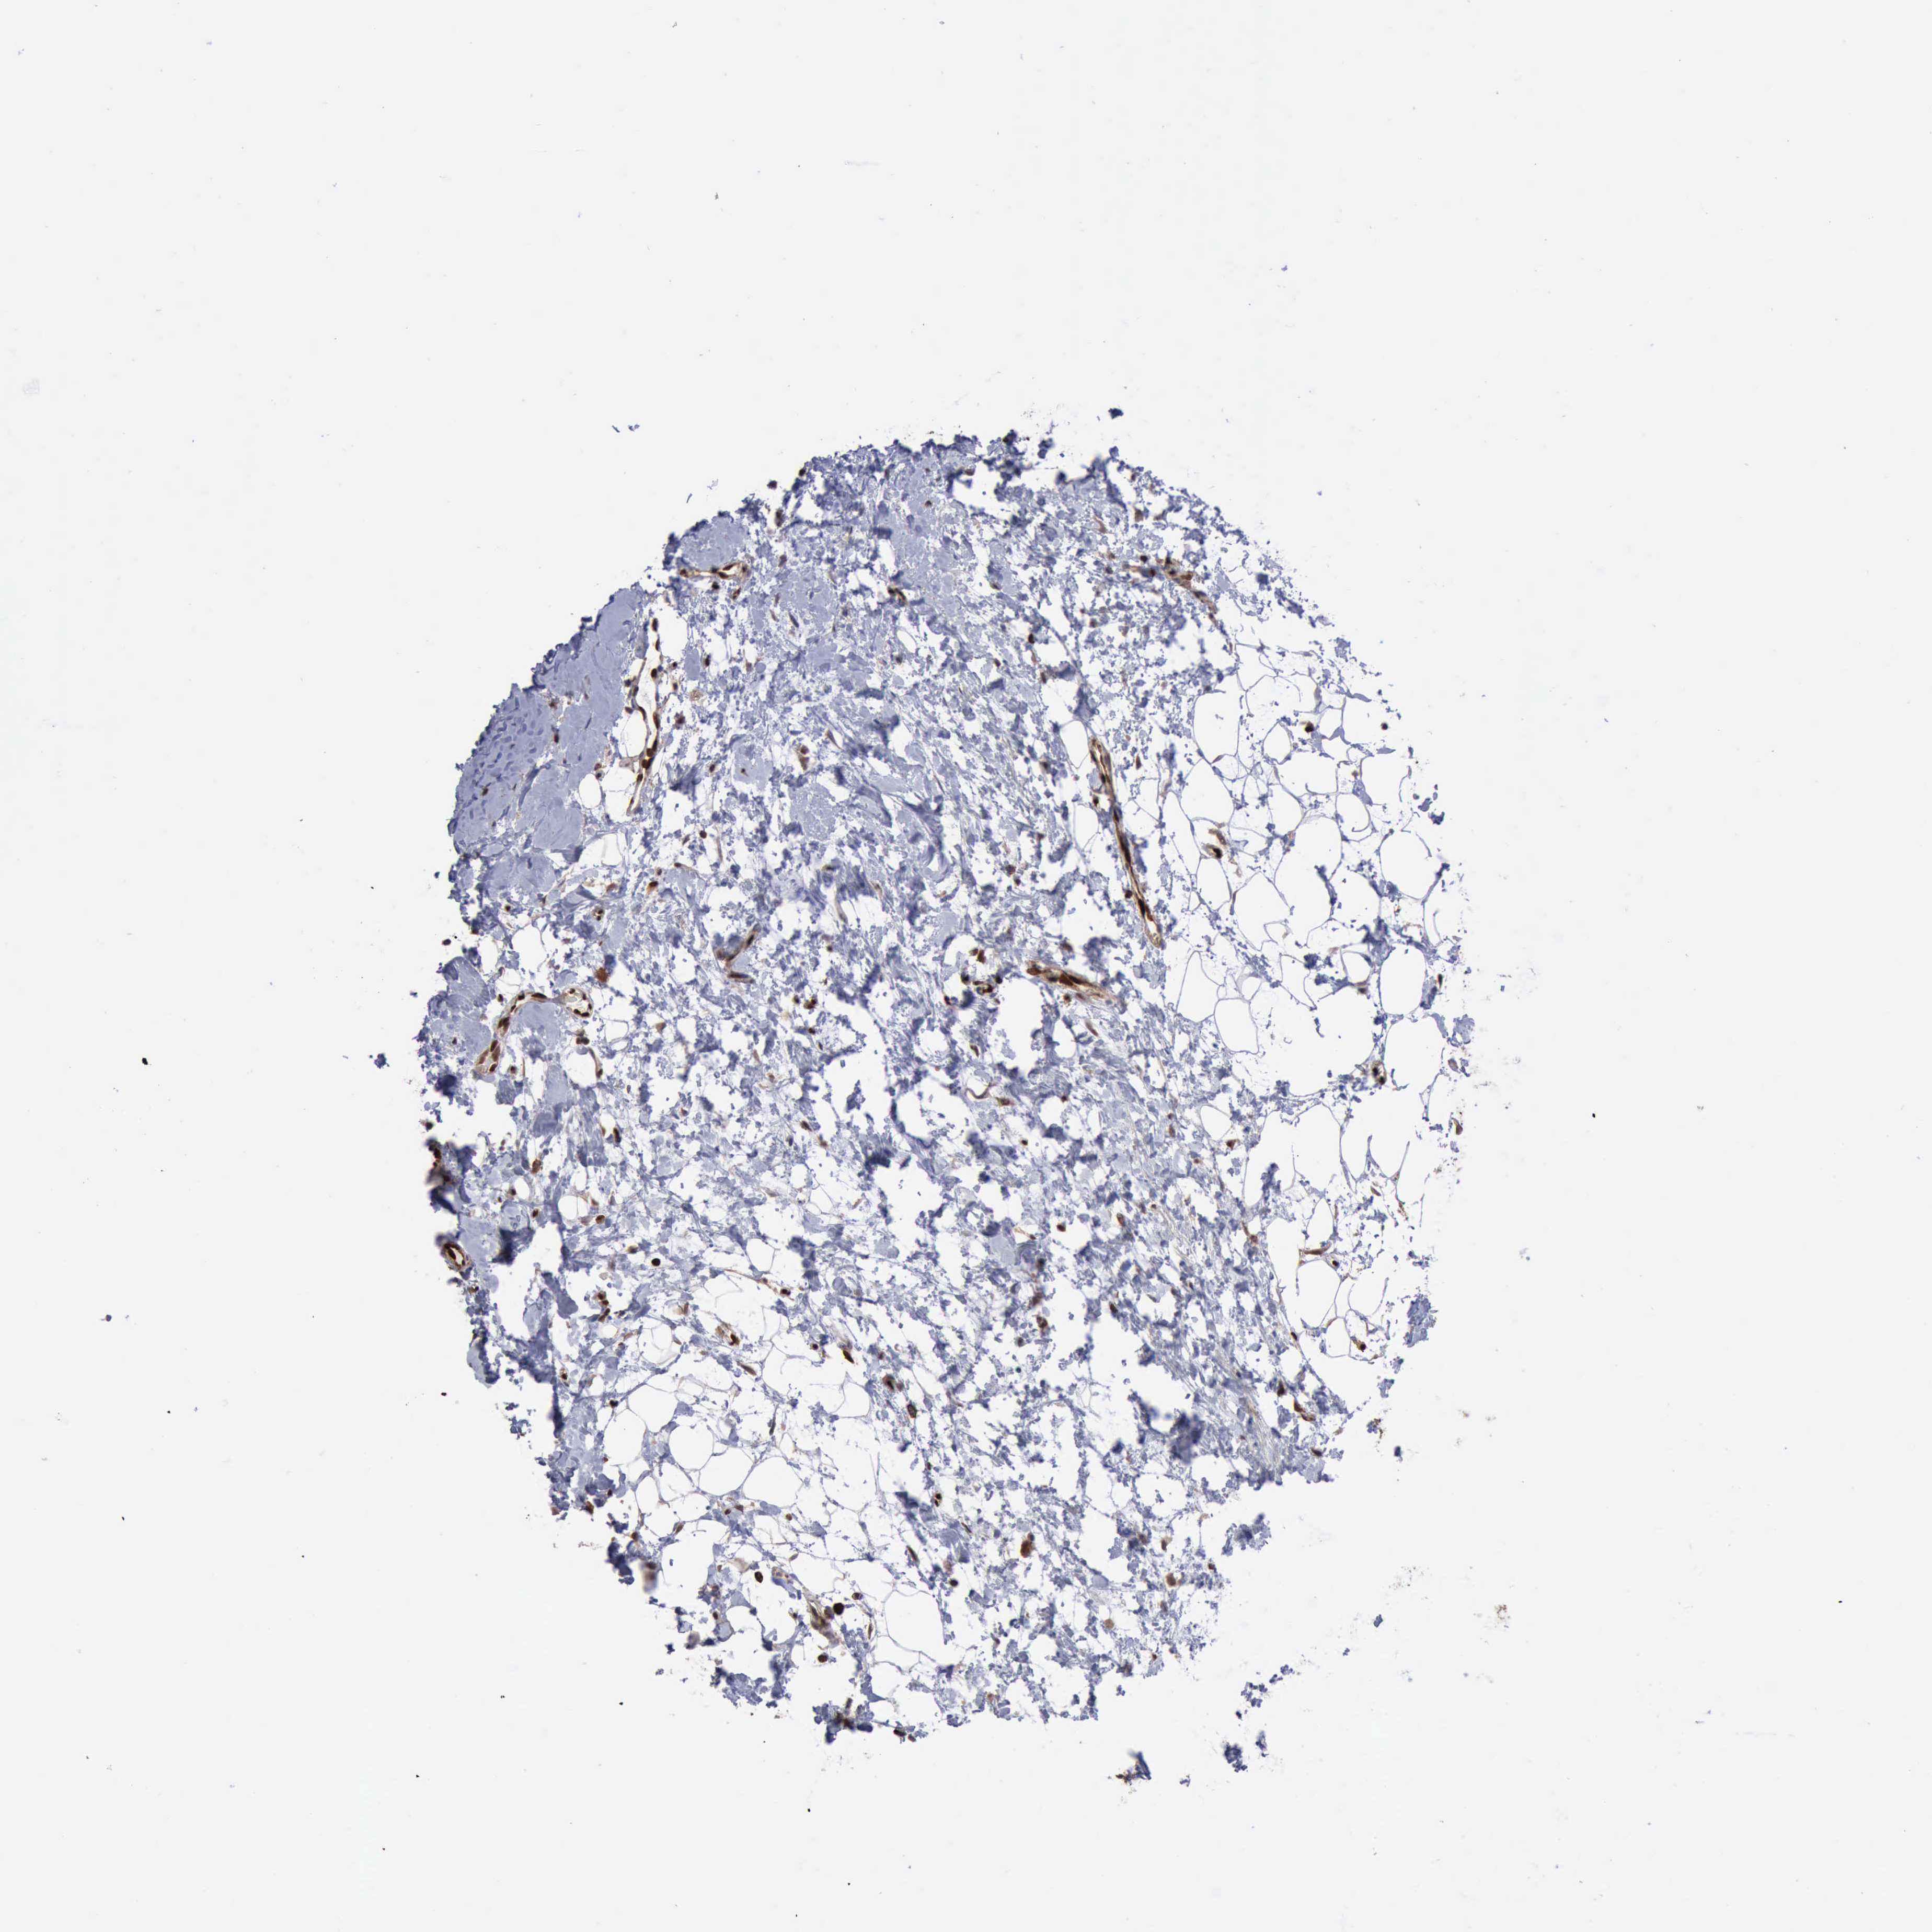

CANCER BREAST CANCER Show tissue menu

BRCA TCGA BRCA VALIDATION PROTEIN EXPRESSION

Breast cancer

Human cancer